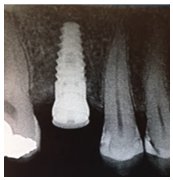

From Left to right; 1. Radiograph of placed implant with healing abutment. 2. Photograph of healed gingiva 10-weeks post-op. 3. Radiograph 1-year post-op. 4. Photograph 1-year post op of restored implant.

Patient presented 10-weeks after the implant placement, proper osseointegration was confirmed and the fixture was restored by a specialist Prosthodontist. At the 1-year supportive periodontal appointment, a diagnosis of healthy peri-implant tissues was confirmed (Figure 3 and 4).